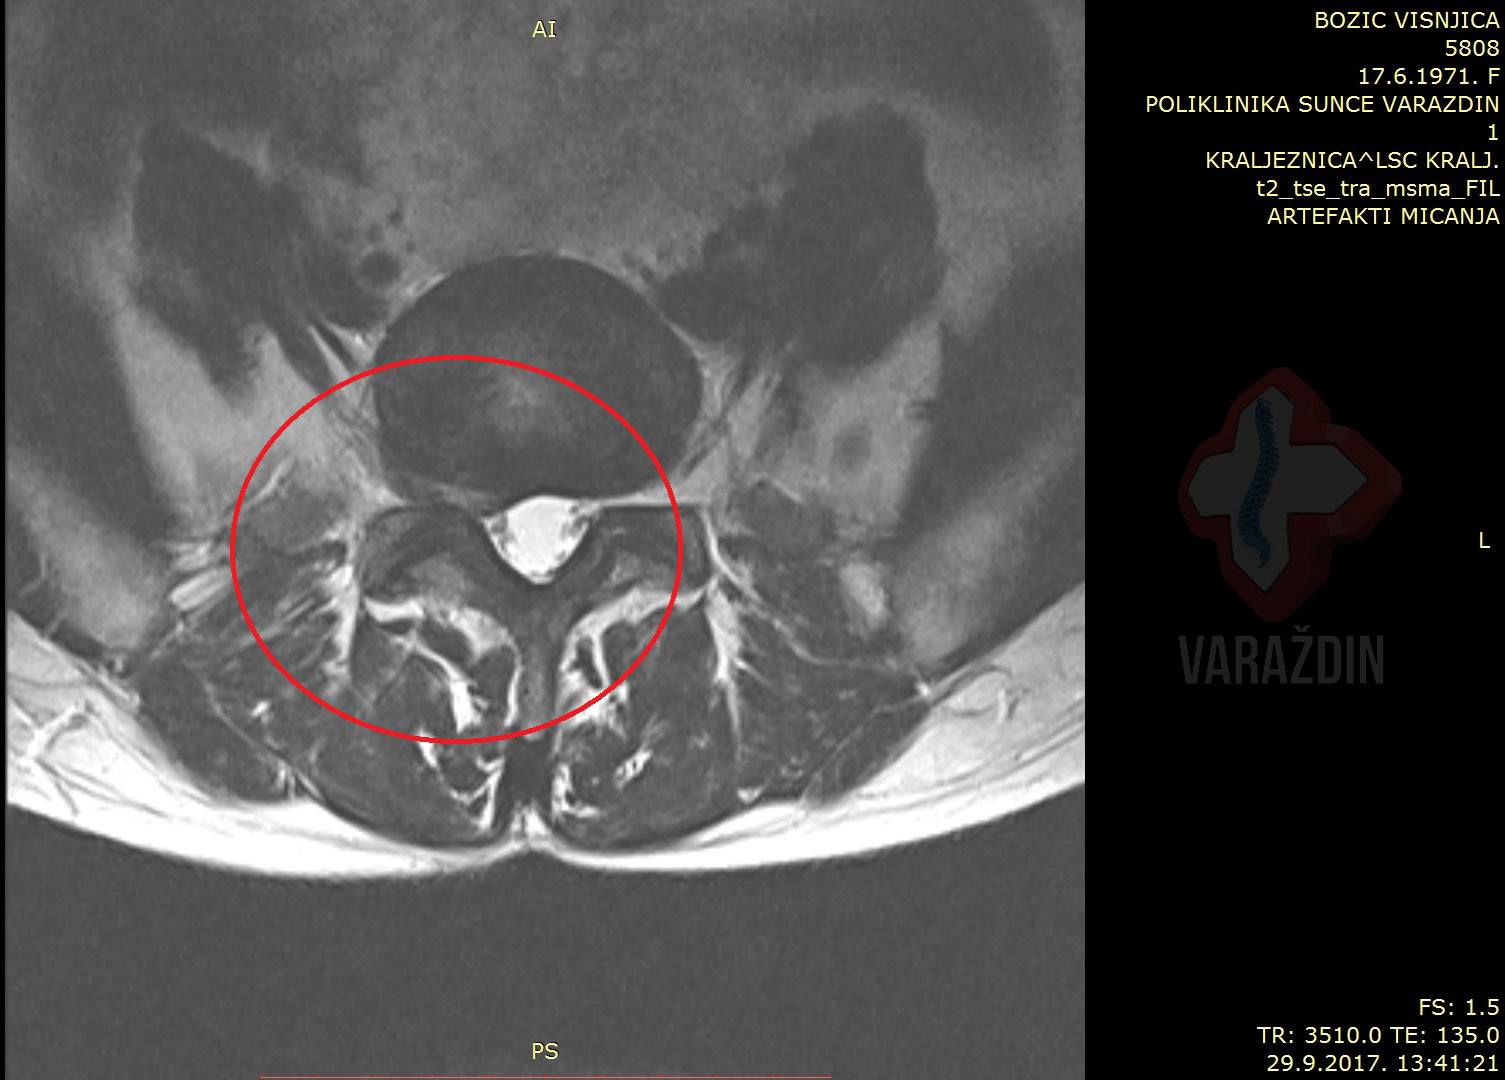

Primjer 6

Gospođa Višnja Božić javila nam se zbog izuzetno

jakih bolova koji su sezali iz lumbalnog područja kralježnice duž

desne noge, uz također u nozi prisutne trnce.

Zajedničkom odlukom krenuli smo na tretiranje lumbalne

kralježnice putem dekompresijskih tretmana. U nadi smanjenja

simptoma odluka je pala na 15-tak tretmana zbog izrazitog

ispupčenja diska na desnu stranu.

Strpljenje gospođe Božić urodilo je plodom: maksimalnom sanacijom

njenog problema. Bol i trnci u desnoj nozi potpuno su nestali.

Zahvaljujemo se na ukazanom povjerenju gospođi Višnji, a

rezultate i efekt tretmana vidjeti možete na slikama MR uz

objavu.